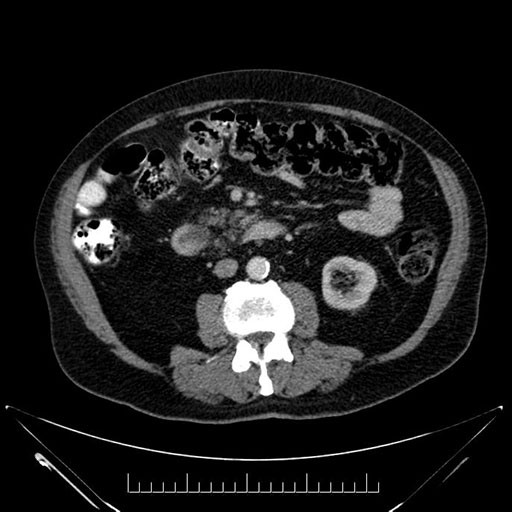

Whipple (pancreaticoduodenectomy) [case 7]

Imaging Analysis

Look through the patient's CT scan to identify any areas of concern for the necessary procedure.

Based on your CT findings, which issue(s) would give reason for "planned slowing down moment(s)" in this case?

Considering a standard Whipple procedure, what step(s) of the operation would you do differently in this case?